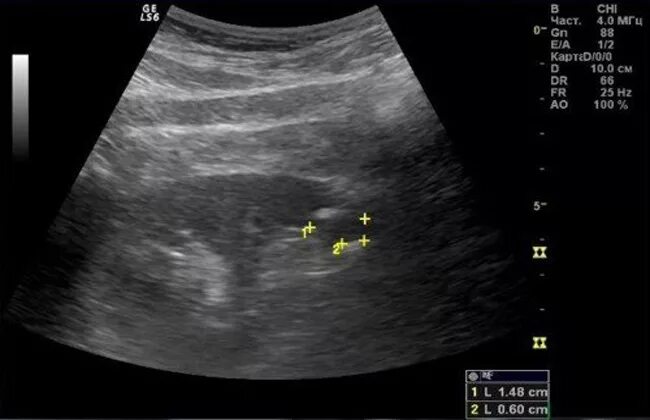

Диффузные изменения паренхимы почек что это